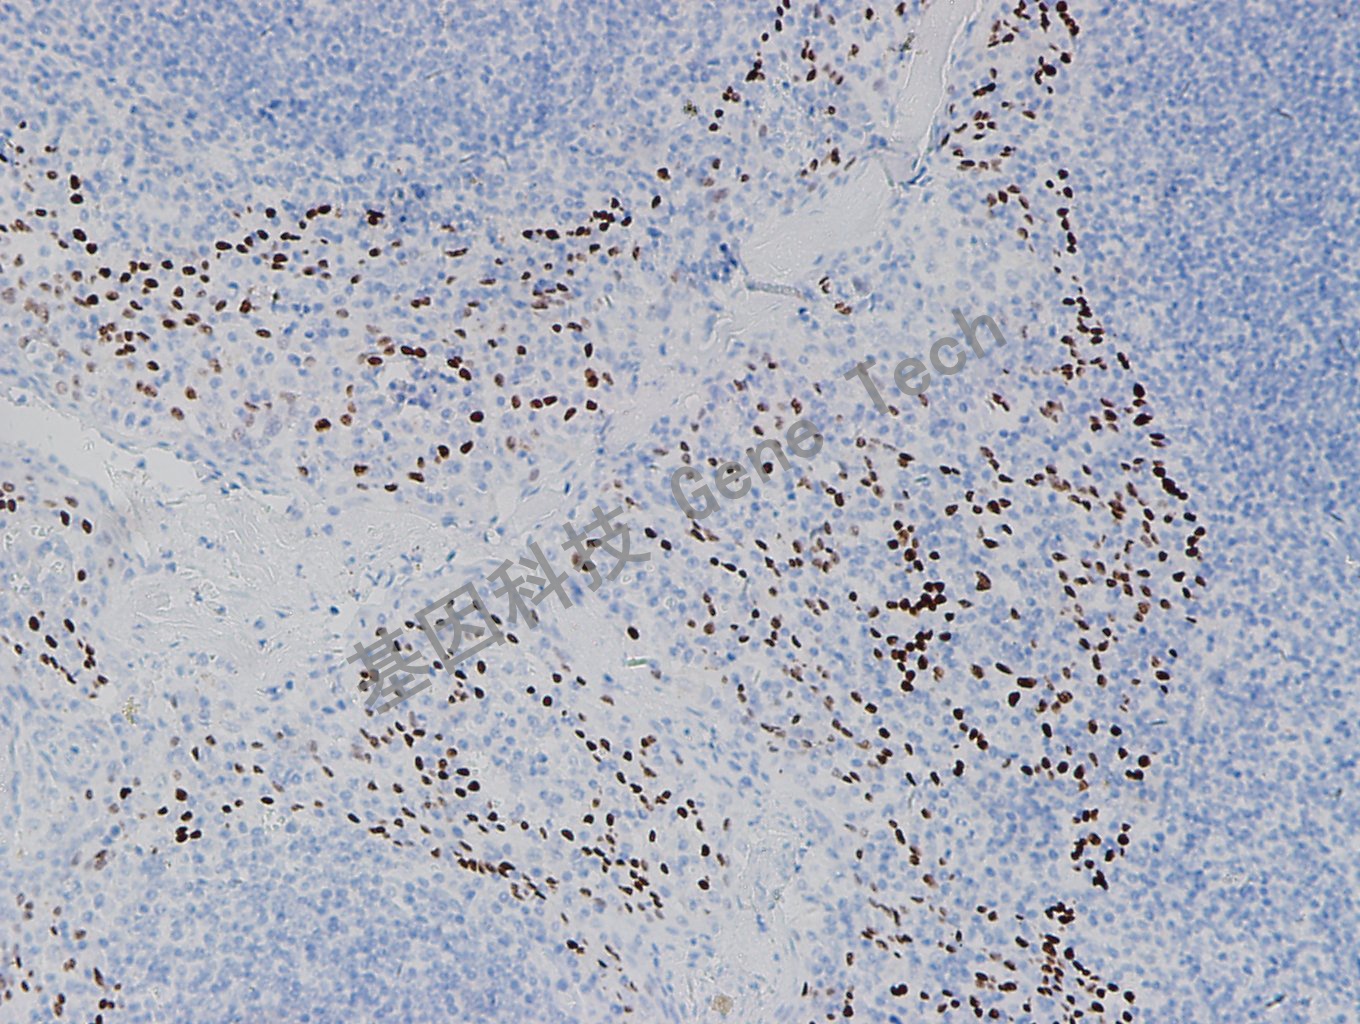

扁桃体石蜡切片,用 p40(GT2338)染色,细胞核阳性 ,DAB 显色。